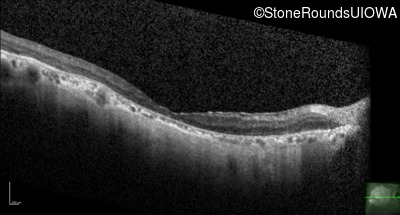

OCT Stack

20/160 sc

20/250 sc

20/200 sc

10/200 sc